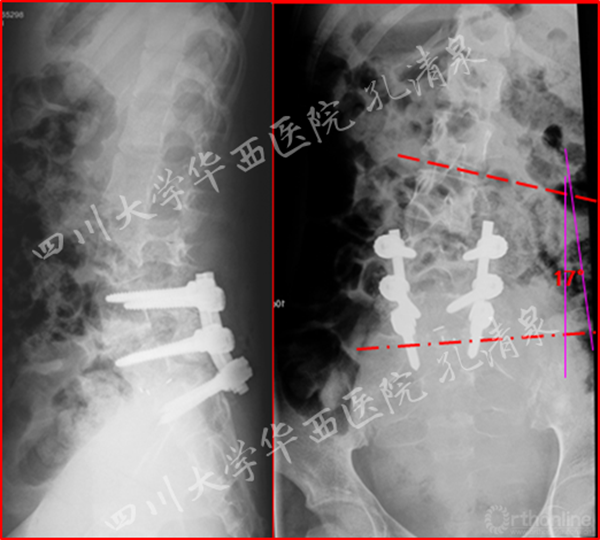

图4 术后复查 侧凸残留17°

图5 术后矢状面CT重建显示复位情况良好